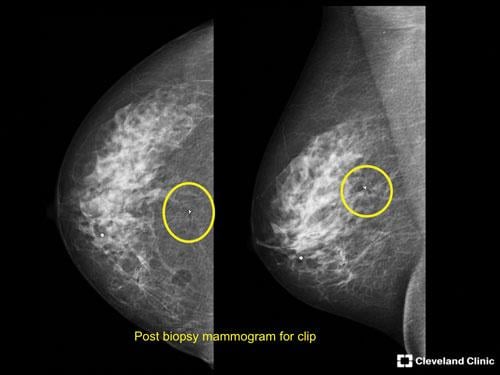

This image shows a 52-year-old patient with benign calcifications in her pre-stereotactic breast biopsy screening.